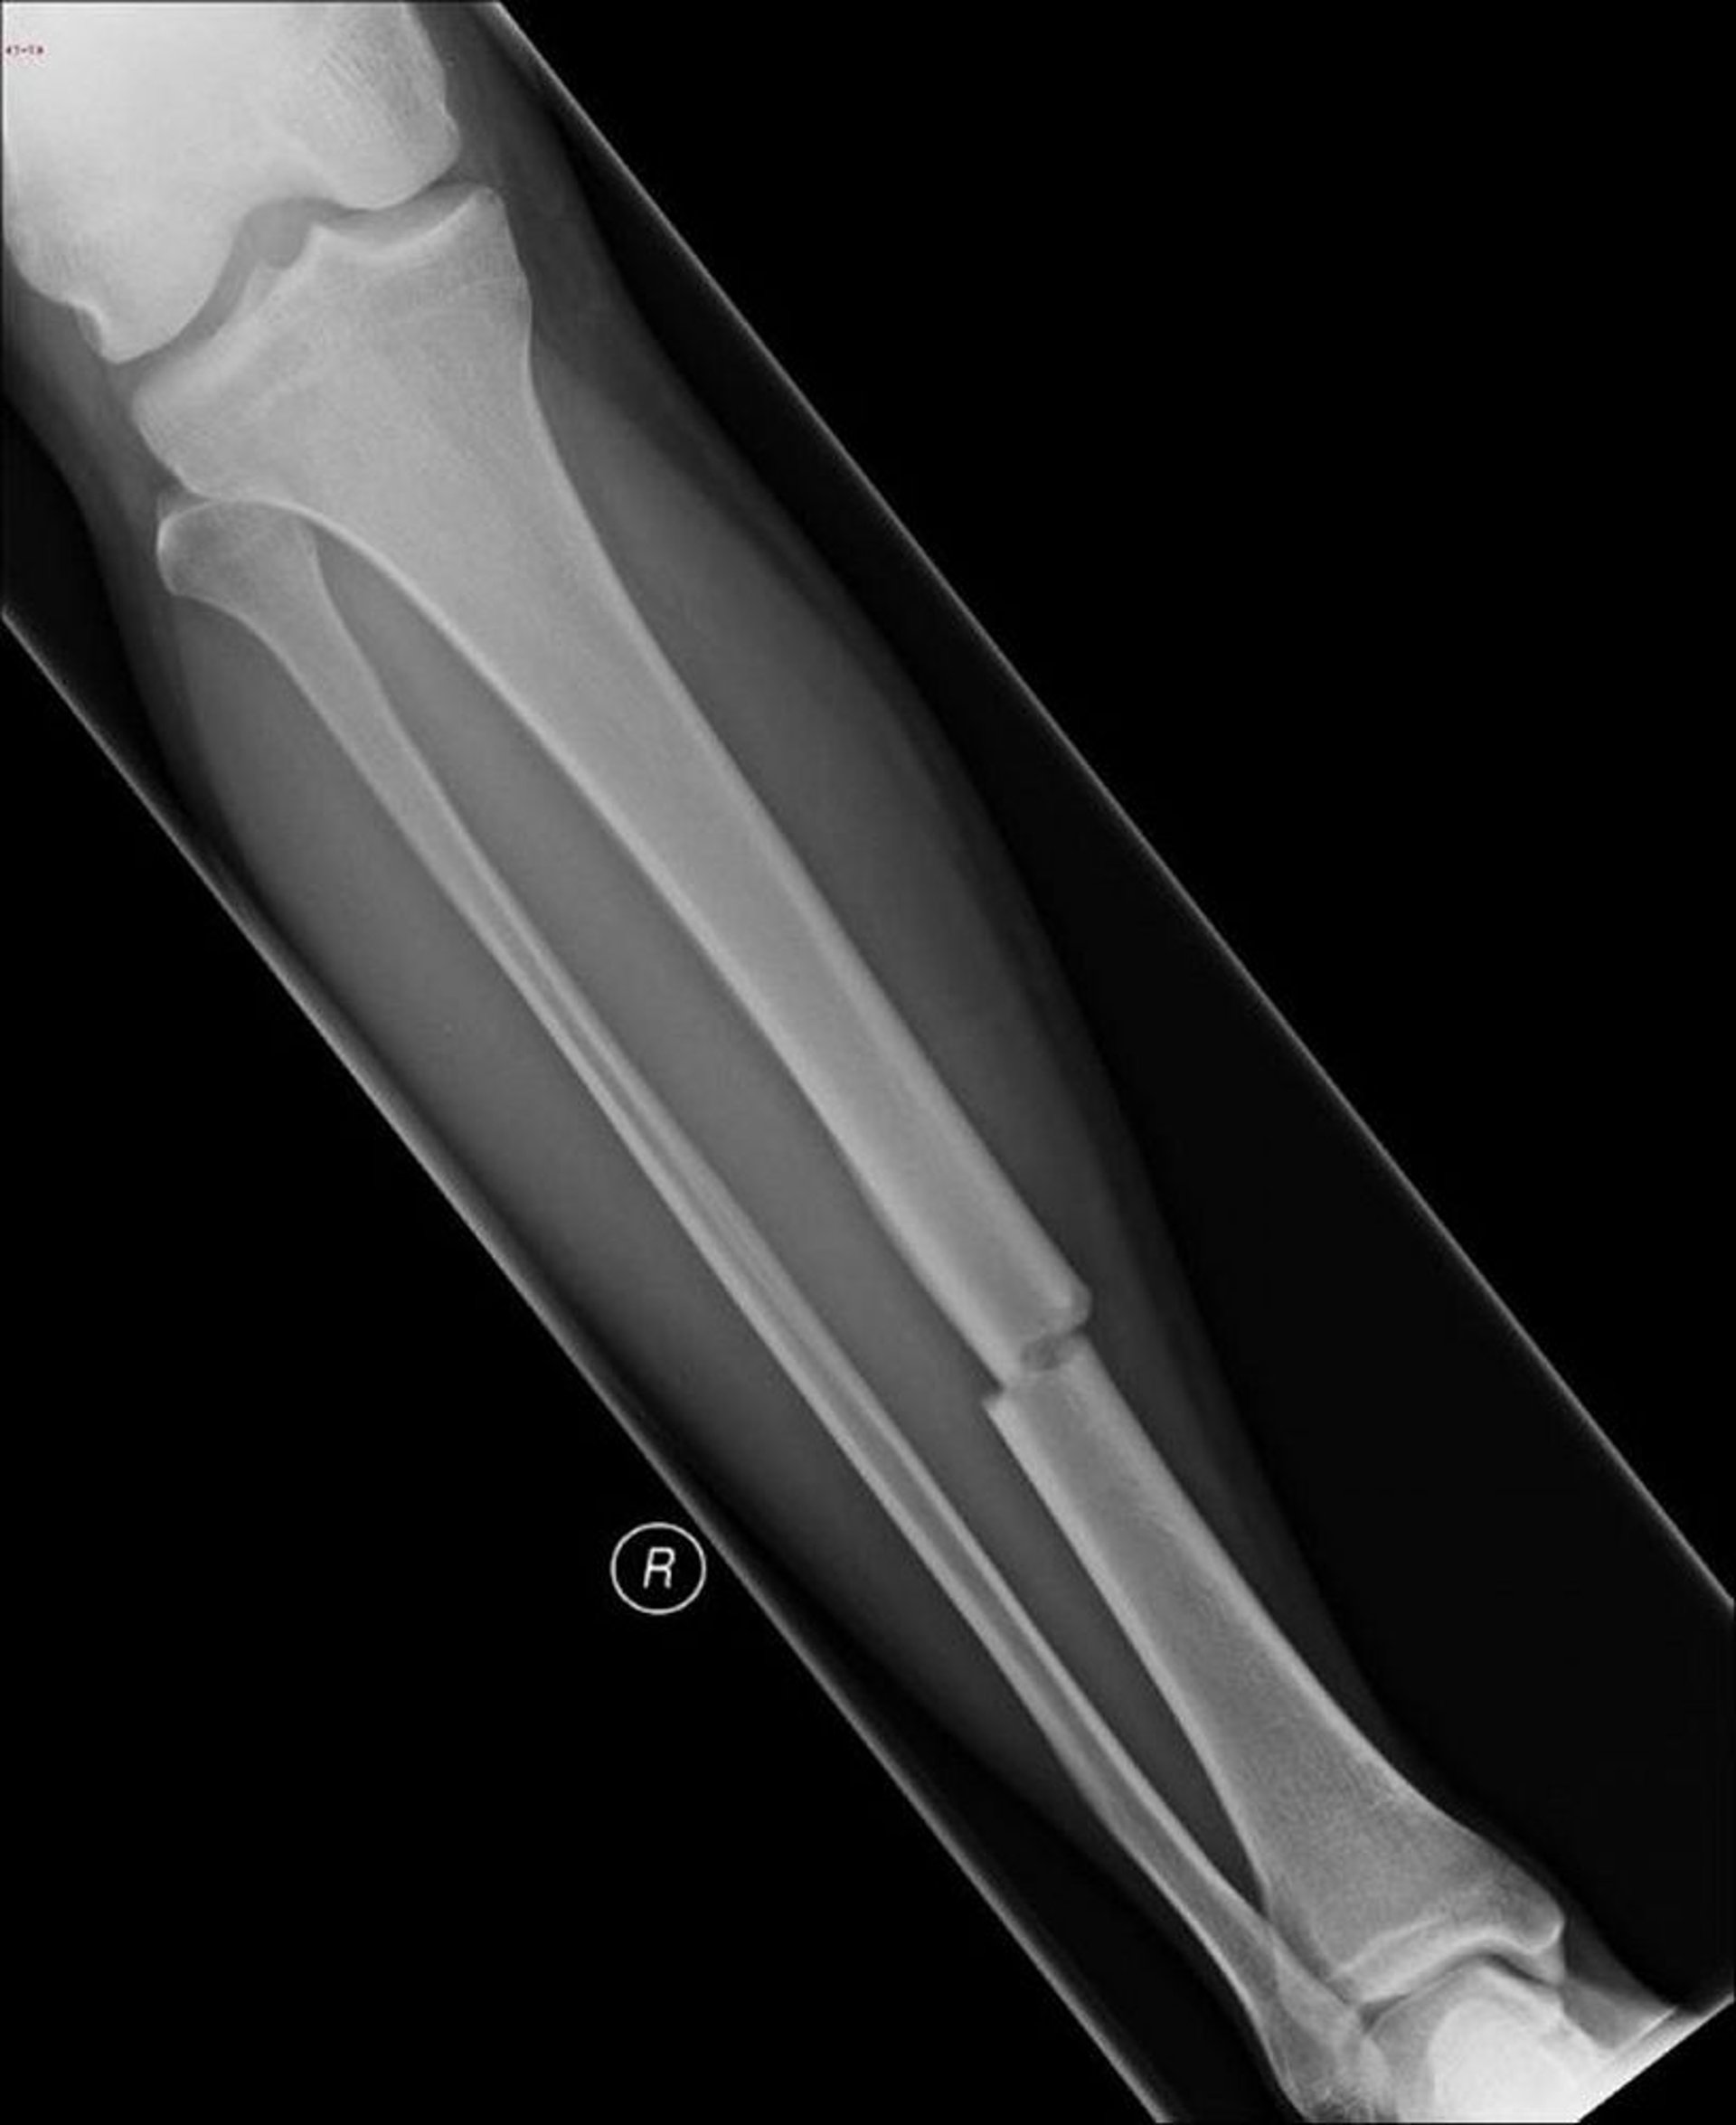

Gebrochenes Schienbein (Tibia)

Auf dieser Röntgenaufnahme ist ein Bruch in der Mitte des Schienbeins (Tibia) zu sehen.

Bild mit freundlicher Genehmigung von Dr. med. Danielle Campagne.